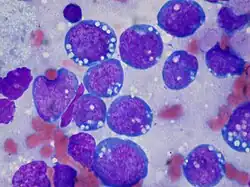

Blood, Bone Marrow and Immune System